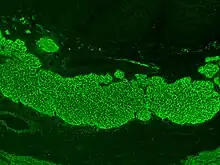

Historically three other antibodies were measured: anti-reticulin (ARA), anti-gliadin (AGA) and anti-endomysial (EMA) antibodies.[92] ARA testing, however, is not accurate enough for routine diagnostic use.[93] Serology may be unreliable in young children, with anti-gliadin performing somewhat better than other tests in children under five.[92] Serology tests are based on indirect immunofluorescence (reticulin, gliadin and endomysium) or ELISA (gliadin or tissue transglutaminase, tTG).[94]